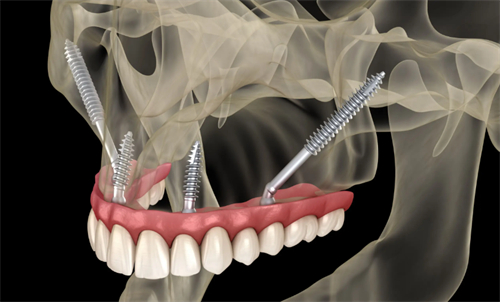

穿颧穿翼种植牙技术的可靠性,首先体现在其显著的生物力学优势上。由于植体更深入骨骼内部,提供了更高的稳定性和支持力,使得种植牙能够长期保持稳固,不易松动或脱落。这一特点对于那些因长期缺牙导致骨量不足的患者来说,尤为重要。此外,穿颧穿翼种植牙手术微创,术后反应轻,患者体验相对舒适,且改善期较短,大大减轻了患者的痛苦和不便。

值得注意的是,穿颧穿翼种植牙并非适用于所有患者。对于高龄患者或患有重度全身性疾病的患者来说,手术风险可能更高,需要在术前进行全方面评估,以确定是否适宜进行此类手术。同时,患者在术后也应注意口腔卫生和护理,定期到医院进行复查和维护,以延长种植牙的使用寿命和保持口腔健康。